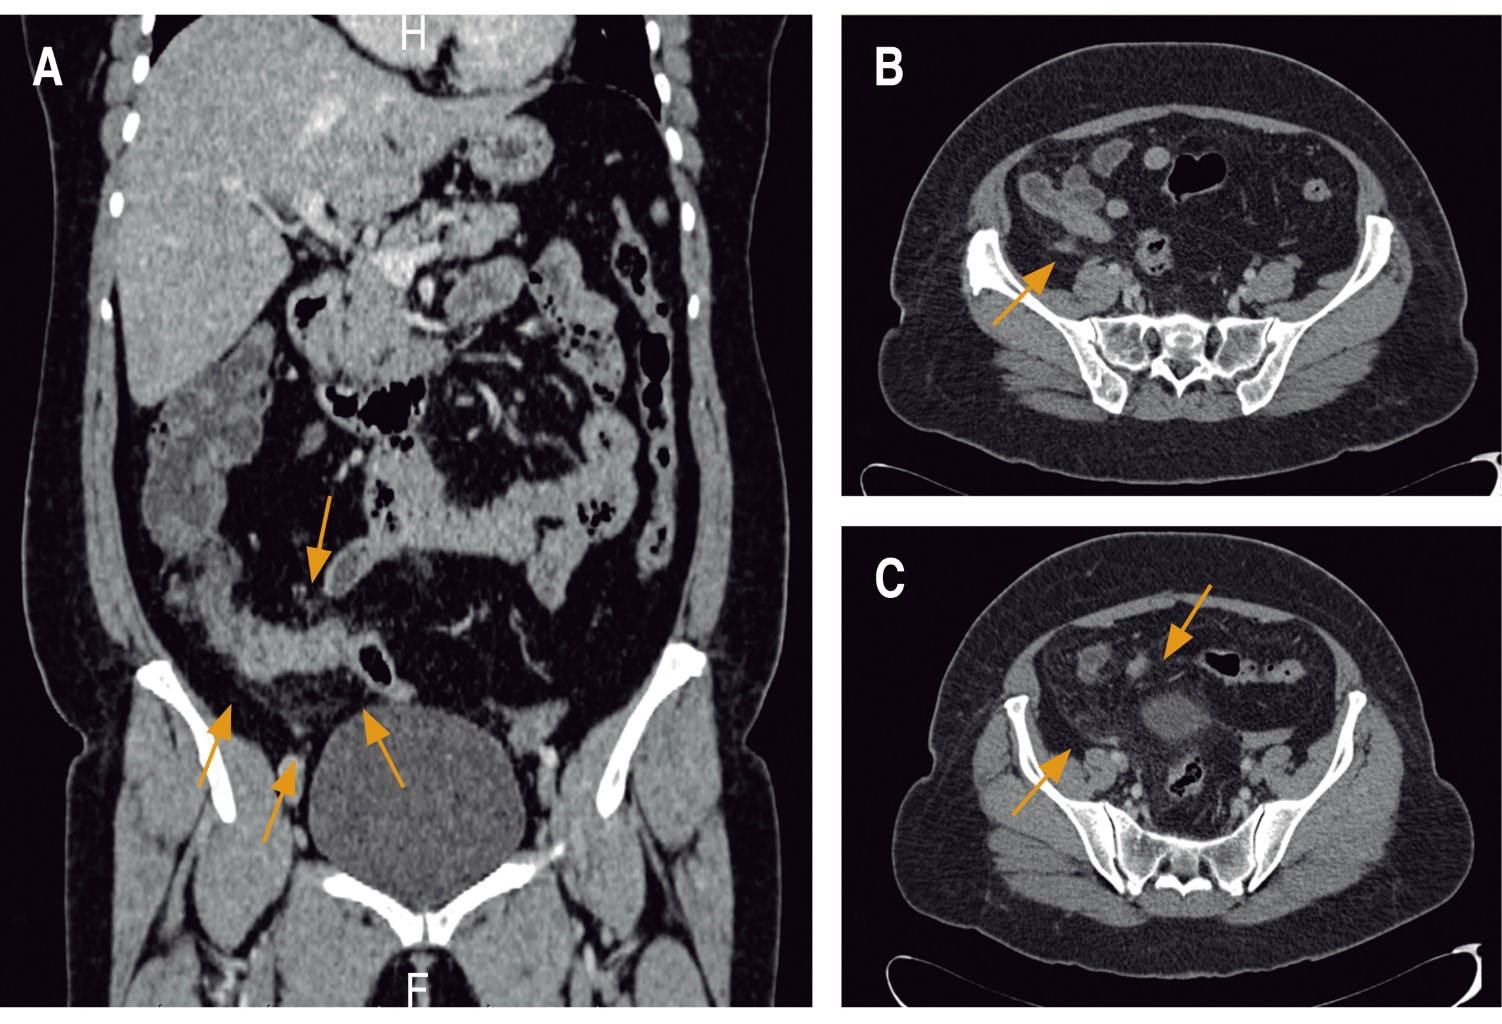

A la exploración física se encontró con dolor en el abdomen a la palpación profunda en fosa iliaca derecha; punto de McBurney; signo de obturador, psoas y signo de Von Blumberg positivos; puntos ureterales derechos superior y medio; Giordano derecho positivo. Se solicitaron exámenes de laboratorio (biometría hemática, química sanguínea y reactantes de fase aguda) que mostraron como únicos hallazgos importantes leucocitosis a expensas de neutrofilia en 94% y proteína C reactiva en 4.3 mg/dl. Como estudios complementarios del cuadro de dolor abdominal se realizó tomografía computarizada de abdomen simple y con contraste intravenoso (Figura 1), sin identificación de apéndice cecal y con cambios inflamatorios en grasa pericolónica del lado derecho, reportado por el Servicio de Radiología.

Figura 1